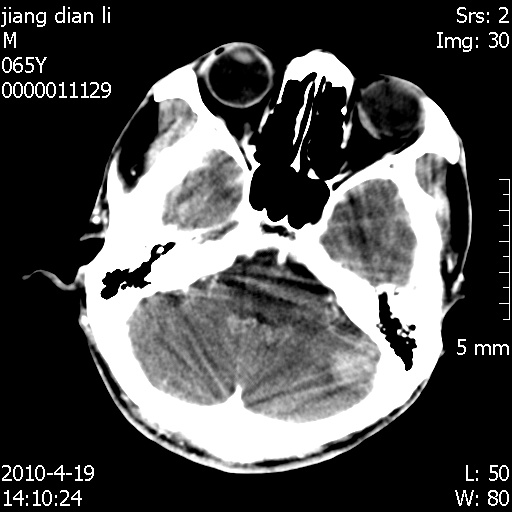

老年男性,突发左下肢无力1天,其余有价值的检查都没有。平扫ct值大约60hu,增强后ct值没什么改变,请大家讨论一下这个病例是什么?说明诊断理由。

左小脑、右大脑顶叶多发圆形高密度病灶,其周环状低密度影。考虑多发脑出血。隔期观察。

今天上班后发现病人前天复查(4月18日发病,19日初诊,22日复查),三个病灶均明显增大,边缘仍旧清楚,水肿加重,右侧脑室基本闭塞。

今天遇到临床医生,询问病人情况,病人已经死亡。

最后看到的病人右侧瞳孔呈针尖大小,估计是继发脑干梗死,而非脑疝死亡。

遗憾! 复习了复查片:发现顶叶出血灶破入侧脑室,侧脑室体部见少许高密度。